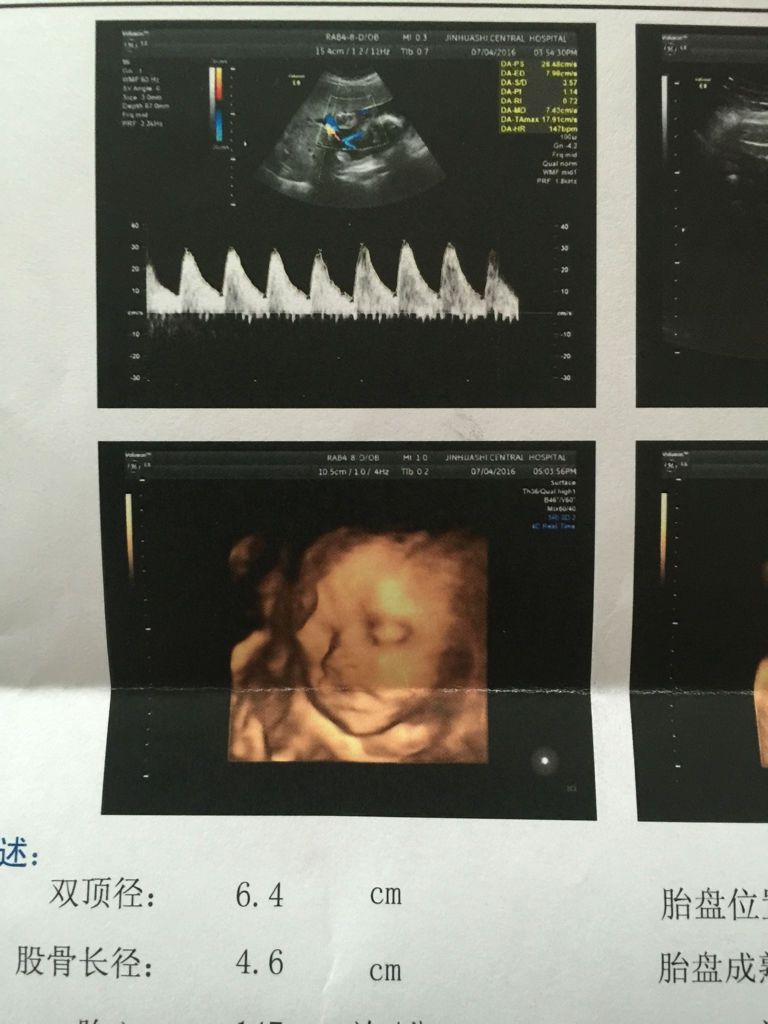

看彩超报告单,求各位大神帮忙辨别男女 男包女宝都好,只是想知道性别,哈哈哈 看彩超报告单,求各位大神帮忙辨别男女。男包女宝都好,只是想知道性别,哈哈哈如题。 点击展开 匿名用户 2016-07-04 18:19 为您推荐: 其他回答 可能是个女宝宝,女宝宝一般圆圆胖胖的。如果男宝宝,应该是偏细长。 捷玛丽_JWYk 2016-07-04 18:21 相关问题 彩超辨别胎儿性别准吗 求大神帮助 彩超报告单显示前壁胎盘能判断胎儿的性别吗 怀孕彩超检查报告单正常么谢谢了,大神帮忙啊